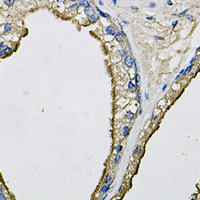

Immunohistochemical analysis of LCN1 staining in human prostate formalin fixed paraffin embedded tissue section. The section was pre-treated using heat mediated antigen retrieval with sodium citrate buffer (pH 6.0). The section was then incubated with the antibody at room temperature and detected using an HRP conjugated compact polymer system. DAB was used as the chromogen. The section was then counterstained with haematoxylin and mounted with DPX.